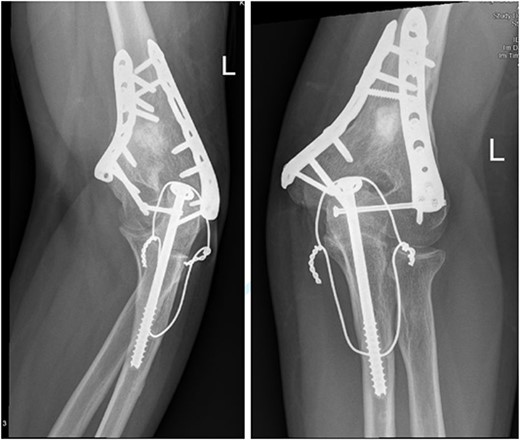

After surgery, the patient was taken back to the ICU and was followed daily by the upper limb orthopedic surgery team for wound care and change of dressings. Four days later, the patient’s condition had improved and he was assessed for distal neurovascular function, which was intact. Afterwards, range of motion was assessed, and no complications were reported before discharge. The patient was kept as an inpatient for almost two more months under the orthopedic trauma team for continuation of management and patient optimization. After discharge, the patient was followed in the orthopedics upper limb and trauma clinic for almost 3 years (Figs 4– 6).

(A). Late follow-up anteroposterior (AP) view of the left elbow after ORIF. (B) Late follow-up lateral view of the left elbow after ORIF.

(A) Late follow-up internal oblique view of the left elbow after ORIF. (B) Late follow-up external oblique view of the left elbow after ORIF.

Our patient was followed afterwards for three years with serial x-rays. No signs of growth arrest or deformity due to our surgical intervention were noted. Instead, on follow up, our patient had a functional range of motion. Elbow range of motion was documented to be 30° extension to almost full flexion and intact pronation and supination. The range of shoulder motion was documented as full. Good healing was observed, but there was some hardware prominence that slightly affected the range of motion, and the patient will be booked for hardware removal. The patient was happy and satisfied about the overall outcome and restored functionality.